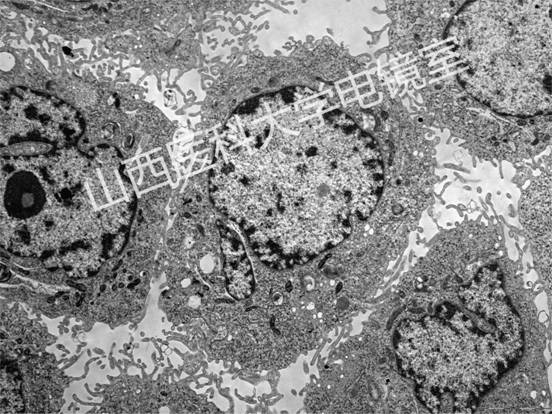

代表性图谱:

破骨细胞

肾

心肌

心肌闰盘

胰腺内分泌细胞

肿瘤细胞

精子

胶原纤维

细菌

材料